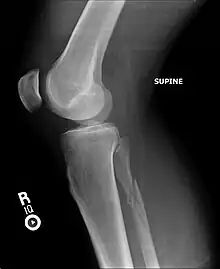

| Segond fracture | Paul Segond | lateral tibial plateau avulsion fracture with anterior cruciate ligament tear | Segond fracture at Who Named It? | ![]() | |